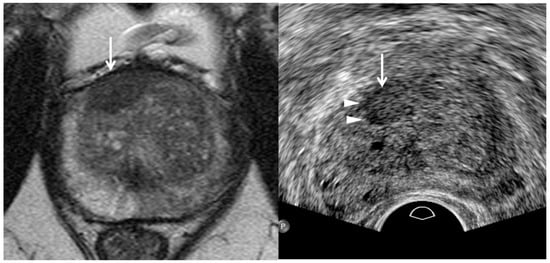

3. TRUS Imaging Features

| Tumor Location/Morphology | MRI | TRUS |

| Scan axis to urethra | Perpendicular | Oblique |

| Anterior 1/3 location | Base and mid-gland | Mid-gland and apex |

| Middle 1/3 location | Same location | Same location |

| Posterior 1/3 location | Apex and mid-gland | Mid-gland and base |

| Tumor size | Different size | Different size |

| Tumor shape | Different shape | Different shape |